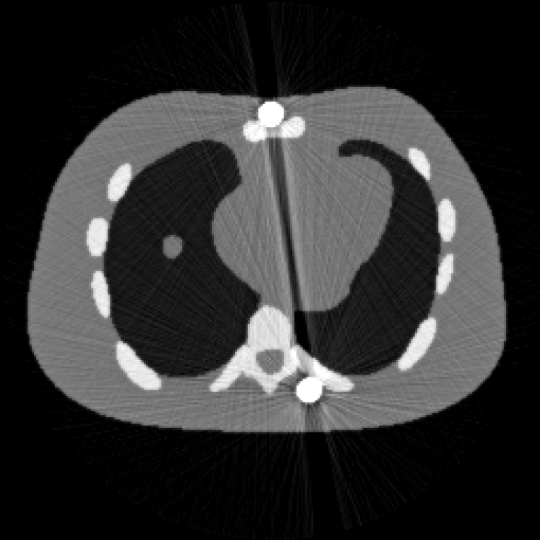

图1 含金属伪影的 NCAT图像 图2 校正后的NCAT 图像

随着医疗技术的进步和新型医用金属材料的不断创新和发展,医疗植入物的需求不断增加,例如骨科植入物、牙科填充物、和冠状动脉支架。但高密度金属假体的存在会使重建的 CT 图像严重退化,导致解剖结构信息丢失,同时伪影的结构可能与某种病灶相似,从而引发误诊等医疗事故。该论文提出一种新的非凸加权变分方法校正金属伪影。不同于常规的使用金属轨迹掩膜的二值化权函数,该方法根据金属伪影在不同区域强度差异,设计了自适应权重,以实现区域性差异化修复从而优化重建效果。进一步采用非凸的

正则化强化边界的对比度,引入图像的有界性约束进一步提升重建精度。基于全变差的预对偶形式,设计了两类有效且全局收敛的一阶原对偶算法求解上述非凸模型。大量数值实验结果验证了该方法的有效性(图1,图2),特别在预分割不准确的情况下,所提出的算法的重建精度得到显著提升。此外,所提出的全分裂算法比当前最具代表性的重加权JSR算法相比,计算速度平均提升两倍。